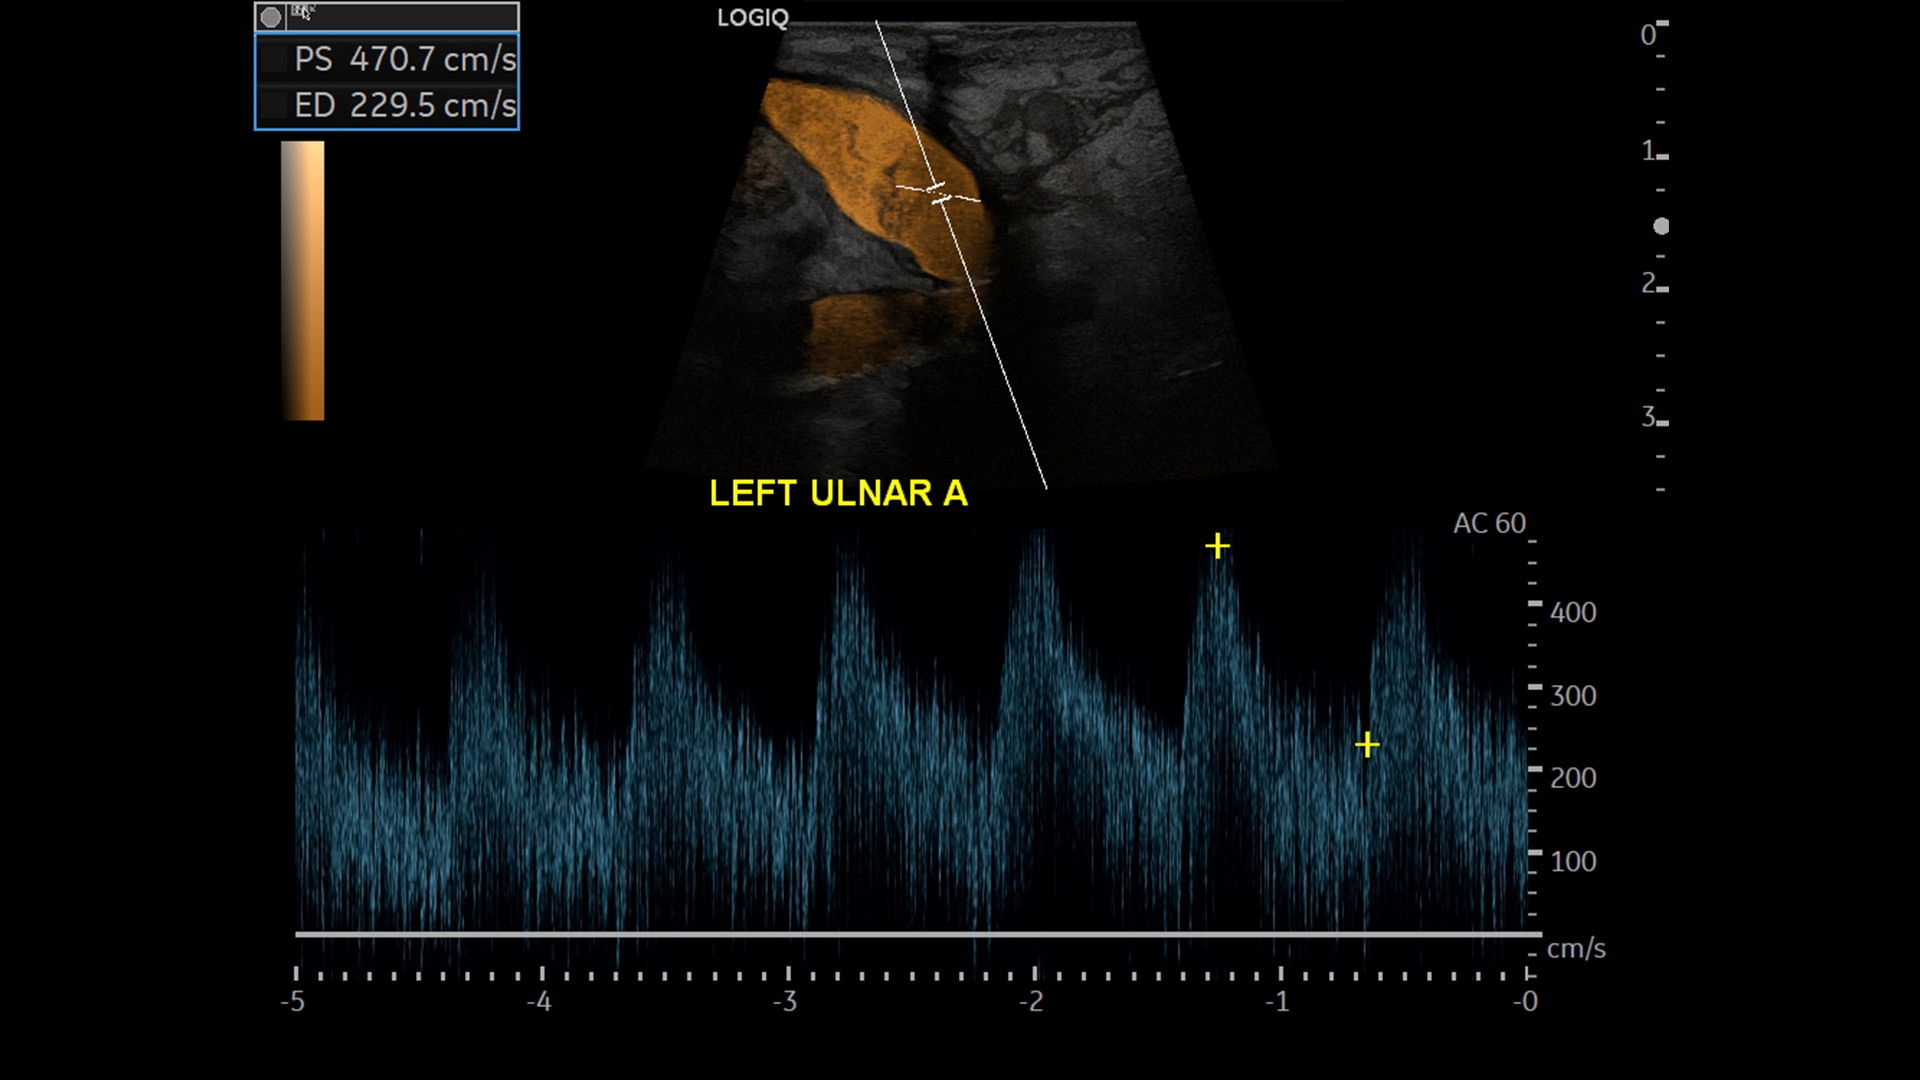

Strength and power to enhance clinical capabilities and deliver exceptional image quality